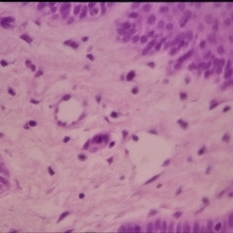

Histopathology of Linear Sebaceous Nevus Syndrome

Histopathology of Linear Sebaceous Nevus Syndrome

Feb 20 2015 by H. Michael Lambert, MD

Histopathology of linear sebaceous nevus syndrome.

Condition/keywords: histopathology, linear nevus sebaceous syndrome